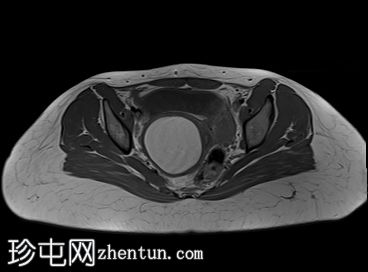

轴位

T1加权像

子宫腔重复畸形,表现为两个子宫体和两个宫颈。

右侧宫颈和子宫腔明显扩张,内部血流信号显示中央狭窄,T1加权像呈高信号,T2加权像呈低信号,脂肪抑制序列图像上无信号下降,内部可见持续低信号灶。最大轴位和冠状位直径分别为约6.5 x 6.4 x 14.2 cm。可见该肿块向前压迫膀胱,向后推移右侧卵巢,并紧贴左侧宫颈。

可见两个阴道腔,共同远端开口长1.6厘米。

左侧卵巢囊肿最大轴径和头尾径分别约为5.7 x 4.3 x 5.5厘米,T2加权像呈高信号,T1加权像呈低信号。

盆腔内可见少量游离液体,可能为生理性积液。